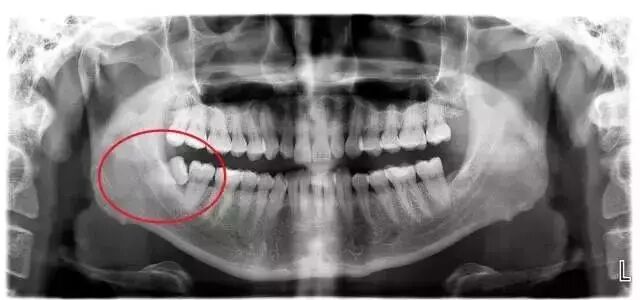

▲智齿的各种生长状态

看看上图这些智齿的生长位置,真是千奇百怪。你觉得那颗最好拔?智齿但一旦生长位置出现了偏差,那就得科普另外一个词,阻生智齿。

▲阻生智齿

智齿在颌骨内由于位置不当,不能萌出到正常咬合位置,被称为阻生智齿。阻生智齿必须拔除,并且拔除的难度远远大于一般智齿。

这种情况你只有通过拍摄口腔全景片才能看清: